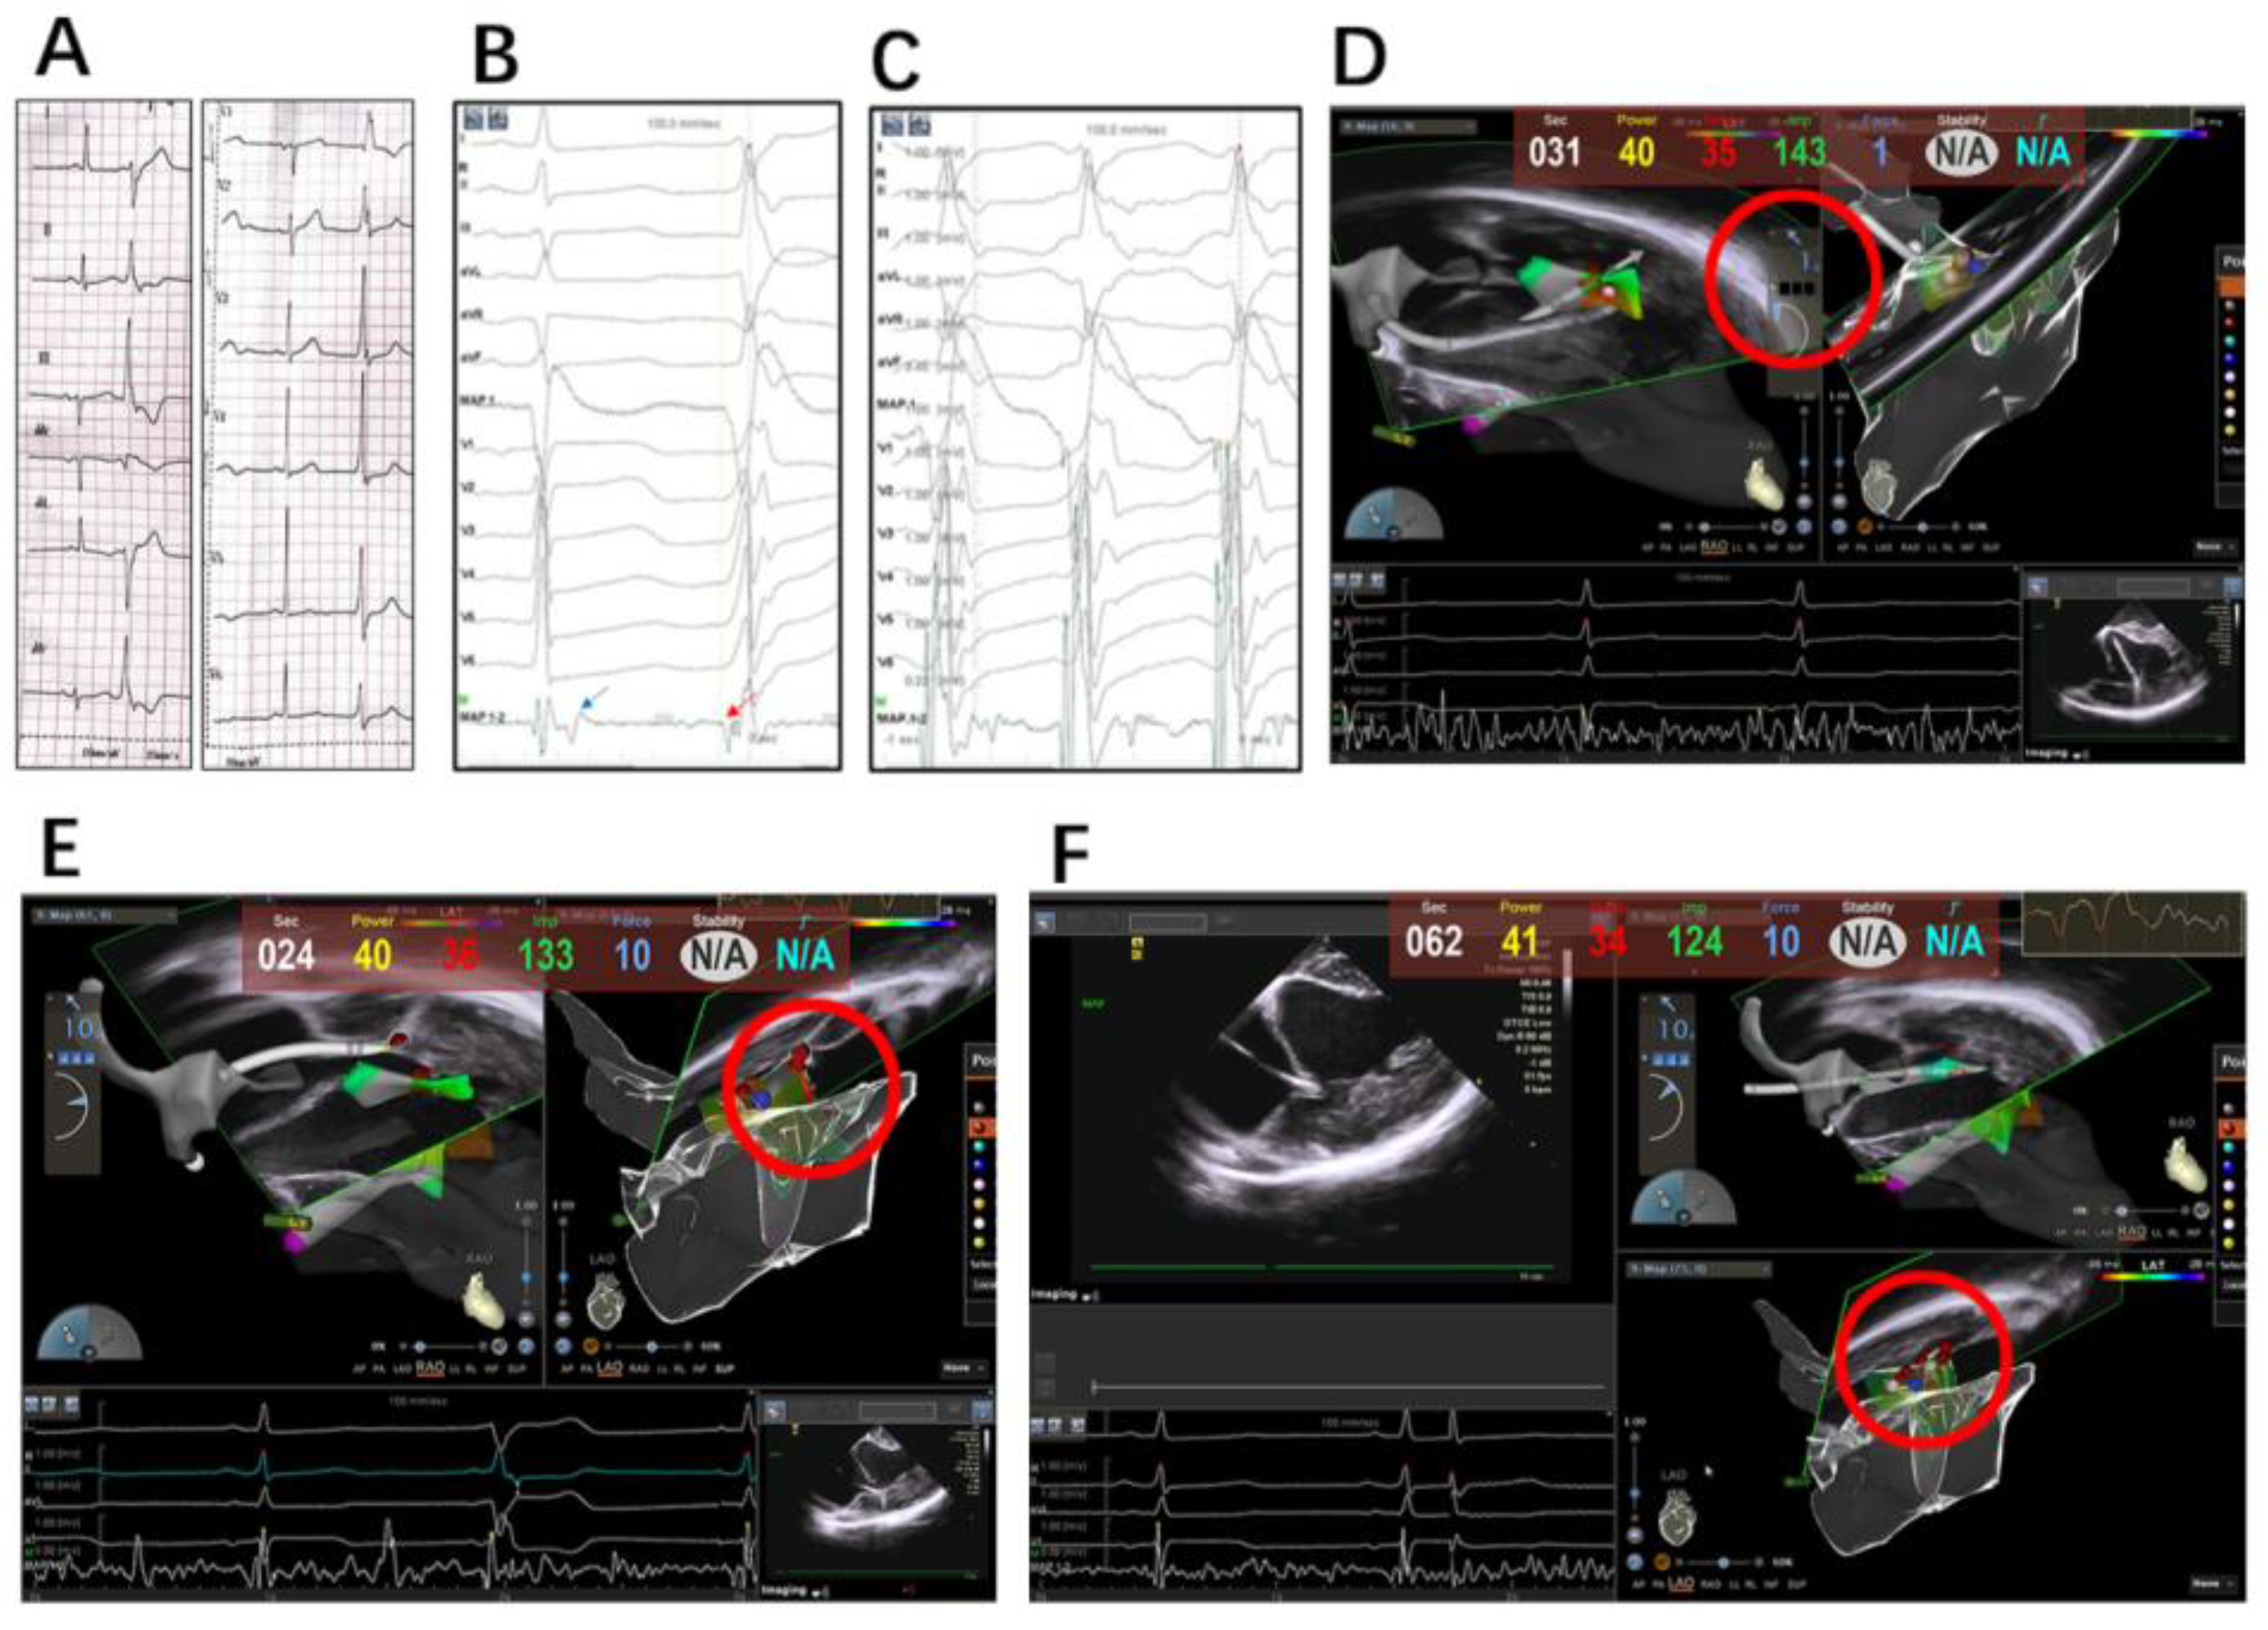

2.2. Electrophysiology Study, Mapping and Ablation

2.2.1. Intracardiac Echocardiography

2.2.2. Mapping and Ablation